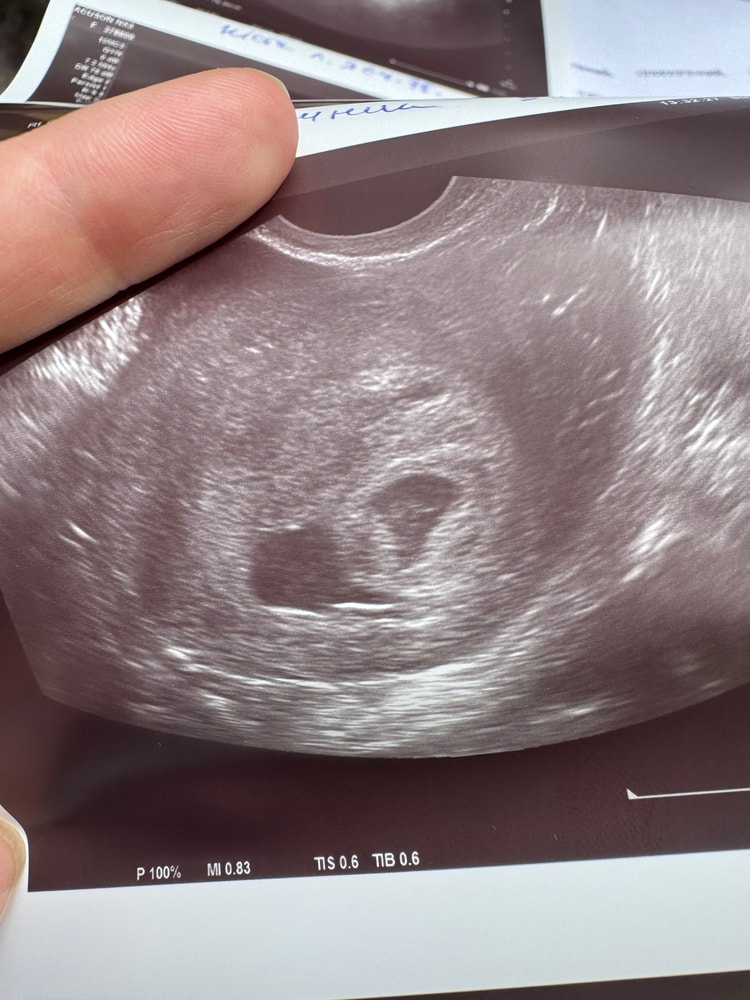

Не внематочная🙏🏻😭 замершая

Кажется, моя эпопея с беременностью проясняется, ПЯ нашли наконец-то, главное с жт внутри, это не псевдо яйцо как при внематочной.

ПЯ небольшое, деформировано, без эмбриона, уже пошла отслойка. Но на этом приключения не заканчиваются, так как киста на яичнике выросла до 75мм и какой метод прерывания будет - под вопросом. Просто выпить таблетку, скорее всего, не получится, потому что киста может лопнуть😓 Но это хотя бы не внематочная, я уже радуюсь и такому на данный момент

Деля , сказали 6 или 8, почему-то не написано в заключении, она сказала оно вытянуто, деформировано

Но желточный мешочек главное проглядывается внутри, но и главне в этой истории, я не написала, что уменьшилось в яичнике ЖТ, хотя оно должно расти если беременность развивается, а оно плавно за 3 предыдущих узи становится меньше